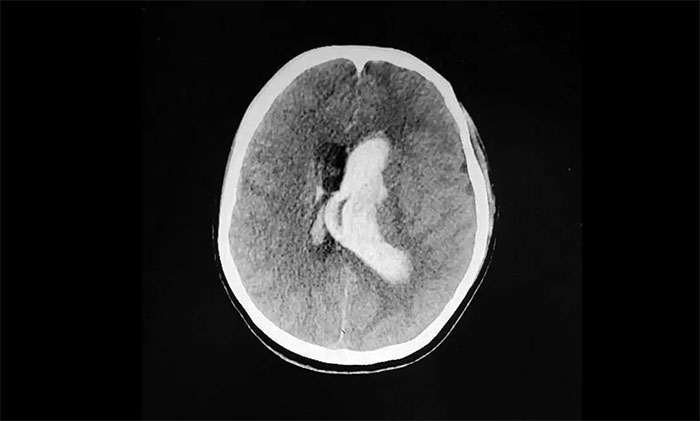

情急之下,家人匆忙將她送到附近醫(yī)院。經(jīng)頭顱CT檢查顯示:腦室出血,左側(cè)腦室、三、四腦室鑄型。

▲ 突發(fā)性腦出血,左側(cè)血腫已突入腦室

腦出血往往起病突然,進(jìn)展迅速。病情與出血部位、出血量及并發(fā)癥有關(guān),致死率很高,急性期為30%-40%。而腦室出血鑄型為腦出血中重癥類型,其往往出血量大,位置深在,病情危急,病死率相當(dāng)高。

時(shí)間就是生命,生命重于一切。通過急診全麻下行雙側(cè)腦室外穿刺引流手術(shù),清除血腫,降低顱內(nèi)壓后,小雨暫時(shí)脫離了生命危險(xiǎn),但仍處于昏迷狀態(tài),并合并有右側(cè)肢體偏癱。